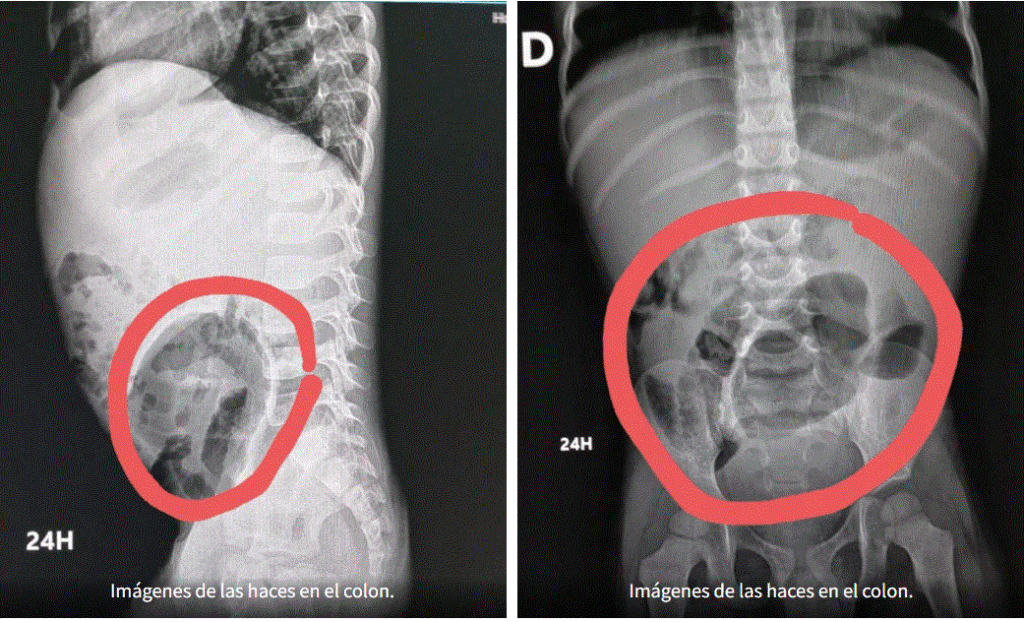

La doctora Idelsa Polanco encargada del departamento de gastroenterología del hospital pediátrico Hugo Mendoza explicó que el megacolon congénito también llamada Enfermedad de Hirschsprung es una ausencia de los ganglios nerviosos de la terminación del intestino, es decir el colon, cuya función es expulsar las heces fecales.

La especialista detalla que si no hay terminación, «la pupú se va acumulando en el colon y no hay quien la expulse hacia afuera y empieza a creer del tamaño de las heces fecales y se va quedando grande».